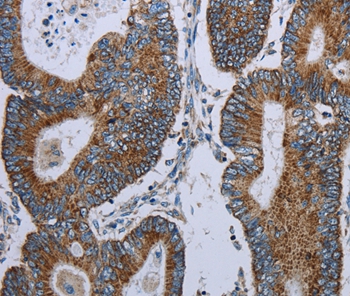

Immunohistochemical analysis of paraffin-embedded Human colon cancer tissue using #37686 at dilution 1/20.

Immunohistochemistry: 1:25-1:100